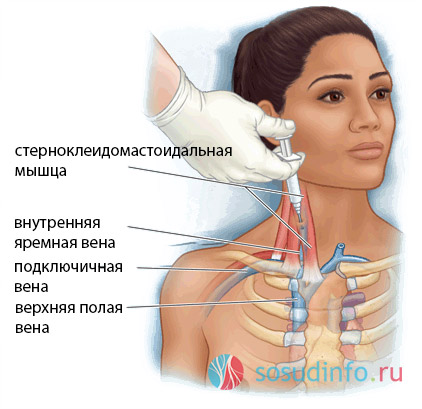

Анатомия внутренней яремной вены: КТ изображения